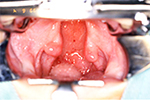

6)口蓋裂の手術

当科では、1歳~1歳2ヶ月に口蓋裂の手術を行っています。この時期に手術をするのは、発音機能と上顎の発育への影響の両面を考慮した結果です。手術が早いと発音機能は良くなり易いのですが、上顎骨の発育が著しく障害されてしまいます。入院期間は9日前後です。

(1)手術法

手術法は、プッシュバック法とファーロー法の2種類を用いています。どちらも発音機能の回復は良好で、85%以上の正常言語獲得ができています。口蓋裂の手術は、単に口蓋の破裂部を閉鎖するのではなく、鼻咽腔閉鎖機能に重要な働きをする口蓋帆挙筋という軟口蓋の筋肉を正常な位置に戻して、左右の筋肉を繋げることが重要です。さらに軟口蓋の長さも延長する必要があります。

このため、プッシュバック法では硬口蓋前方部から粘膜骨膜弁を剥離し、それを後方移動することで軟口蓋を延長します。左右の口蓋帆挙筋は断端同士で縫合されます(図9-1~4)。

一方、ファーロー法では軟口蓋の鼻腔側、口腔側の両方にZ形成といわれる切開を加えて、軟口蓋を延長します。左右の口蓋帆挙筋は重ね合わせられ、繋がることになります(図10-1~4)。

(2)手術法の比較

プッシュバック法は、古くから多くの施設で行われている方法で、正常言語獲得の成績も良好です。しかし先の手術法のところで説明したように、硬口蓋の粘膜骨膜弁を広範に剥離し後方移動するため、術後に骨の露出面が大きくなります。このため上顎骨の発育が障害され、反対咬合(受け口)になる可能性が高いと言われています。

一方、ファーロー法は、硬口蓋の骨露出がほとんどないため、上顎骨の発育障害が少ないと言われています。発音機能の回復はプッシュバック法と変わらないため、優れた方法と言えます。しかし、一期的に硬口蓋も形成すると裂隙幅の大きい症例ではやはり骨露出が大きくなり、軟口蓋の延長も困難となります。この欠点を補い、ファーロー法の利点を生かすため、当科では、1歳時にファーロー法で軟口蓋閉鎖を行い、その6ヵ月後に硬口蓋を閉鎖する手術を行うという2段階の口蓋裂形成法を行っています。